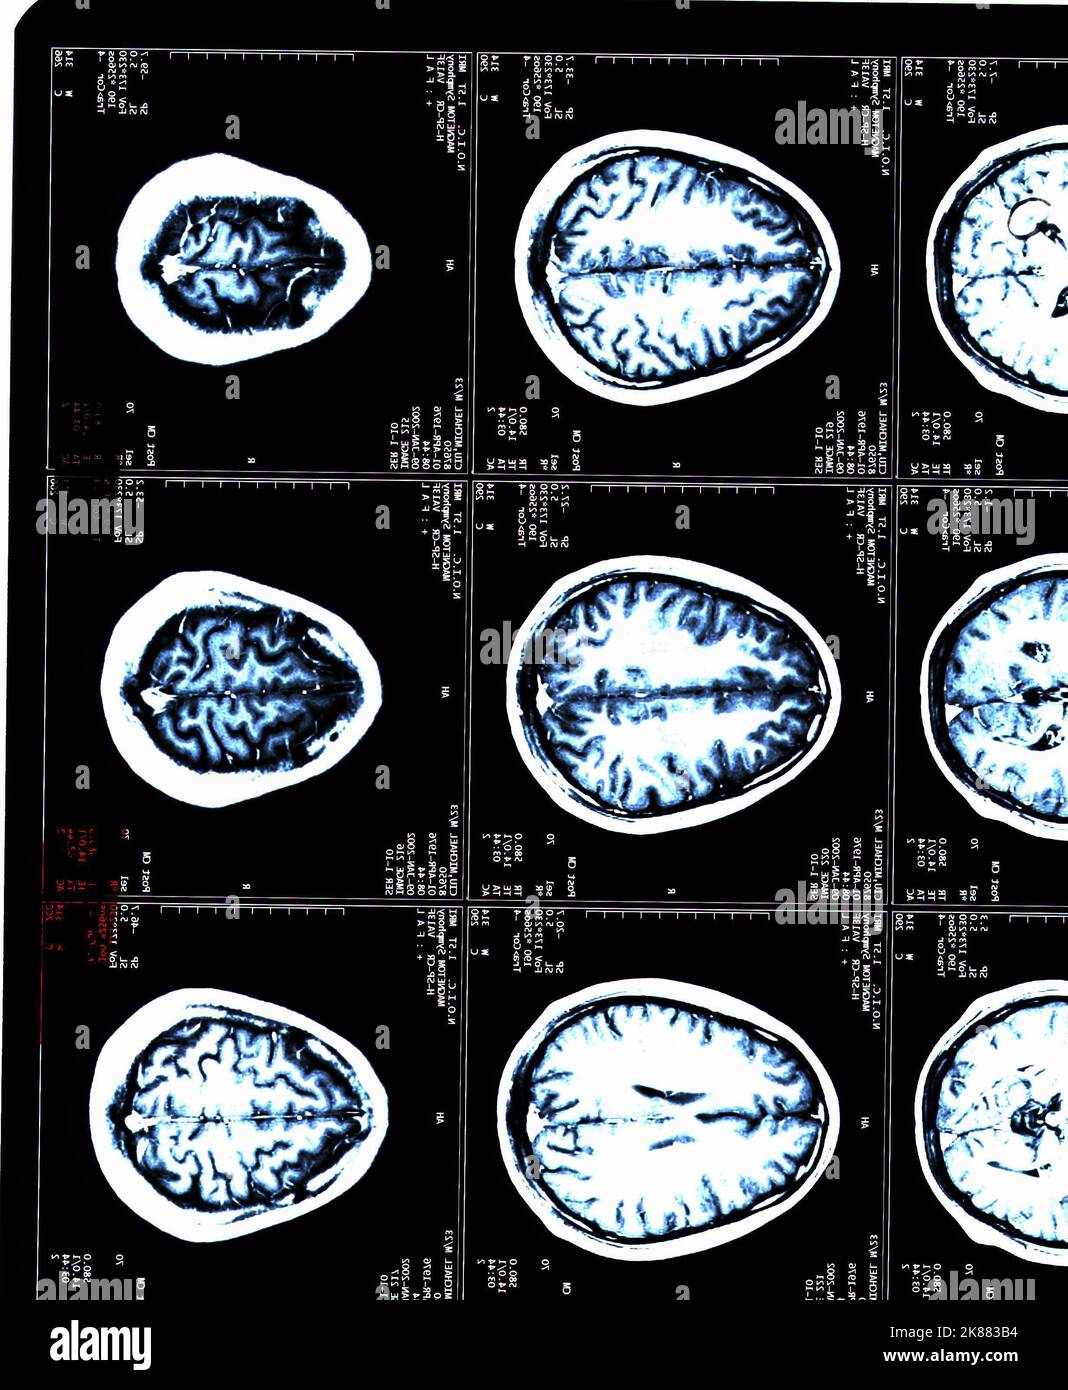

From www.alamy.com

A MRI brain scans of a patient with Multiple Sclerosis Stock Photo Alamy How Often Should Someone With Ms Have An Mri How often you need to get an mri for ms varies, but generally people with ms first have an mri at the time of diagnosis, then again after starting disease modifying. The younger you are or the more aggressive the condition, the more frequently you should receive mri. We recommend an initial cervical and thoracic spine mri with and without. How Often Should Someone With Ms Have An Mri.

A MRI brain scans of a patient with Multiple Sclerosis Stock Photo Alamy How Often Should Someone With Ms Have An Mri Mri with field strength of at least 1.5 t and, preferably, 3.0 t is recommended. For 3d imaging, slice thickness of 1 mm isotropic is preferred but, if not available, should not be. The younger you are or the more aggressive the condition, the more frequently you should receive mri. But, there's lots of factors to consider when deciding how. How Often Should Someone With Ms Have An Mri.